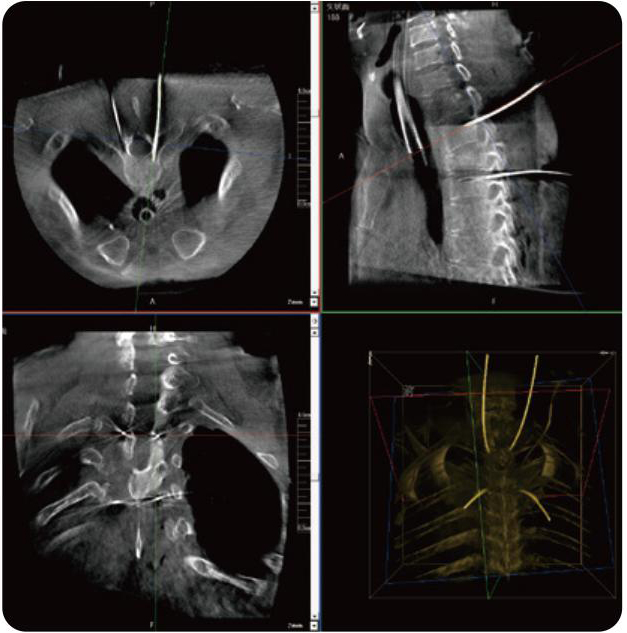

PL300B可應用于多節(jié)段脊柱外科手術,輔助醫(yī)生定位病灶部位,為脊柱外科手術(經(jīng)皮椎體成形術、椎弓根螺釘內固定術等術式)提供術前手術流程規(guī)劃、入釘位置、角度可視化引導,模擬仿真入釘輔助。

PL300B搭配普愛醫(yī)療自主研發(fā)生產(chǎn)的平板3D C形臂,借助一體化自適應配準( 軌跡配準)技術,通過追蹤C形臂三維采集軌跡,自動完成圖像坐標建立和系統(tǒng)坐標配準。配準精度更高,操作步驟少,系統(tǒng)運作效率高。